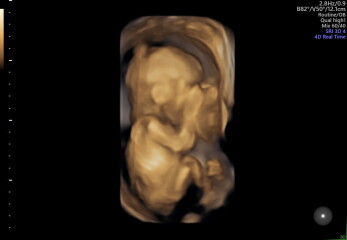

Hi all, had my 20 week scan yesterday. Everything is thankfully going on perfectly in there and there's no concerns. After all my worrying leading up to it I feel a bit numb today about everything baby-wise (although I've been all over with my emotions over the last few months so nothing out of the ordinary really!).

They did a brief 4d bit which I wasn't expecting so I am now too a proud mama to a copper potato :D

@codemytea congrats on the scan - the pics are brilliant!

And @codemytea love the copper potato hahah and congrats that all is well, we got a 4D at early gender scan but it is just so so creepy I’ve barely looked at it haha. Who knew the NHS do this now though? That’s fun!